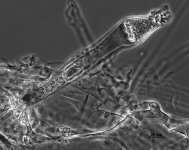

| Species Name: | Saksenaea erythrospora |

| Taxonomy: | FUNGI Mucoromycota, Mucoromycetes, Mucorales, Saksenaeaceae |

| Substrate: | blood, male 26 yr, with extensive burns following IED war wound (Middle East); histopathology + for broad hyphae | Location: | USA Texas, San Antonio, San Antonio Military Medical Center (GEO: 29.46,-98.417) |

| Characters: | CULTURE CONDITIONS good sporulation on Czapek agar at 30-35C - fide submitting lab & UAMH // HUMAN/ ANIMAL PATHOGEN invasive mucormycosis in war wound patient - Hospenthal DR, Chung KK, Lairet K, Thompson EH, Guarro J, Renz EM, Sutton DA, J Clin Microbiol, 49:3707-3709, 2011 // HUMAN/ ANIMAL PATHOGEN war wound - Alvarez E, Garcia-Hermoso D, Sutton DA, et al, J Clin Microbiol 48:4410-4416, 2010 // THERMOTOLERANT opt. 25C; grows at 42C; NG at 50C - fide submitting lab (Click for publications citing UAMH 11526) |